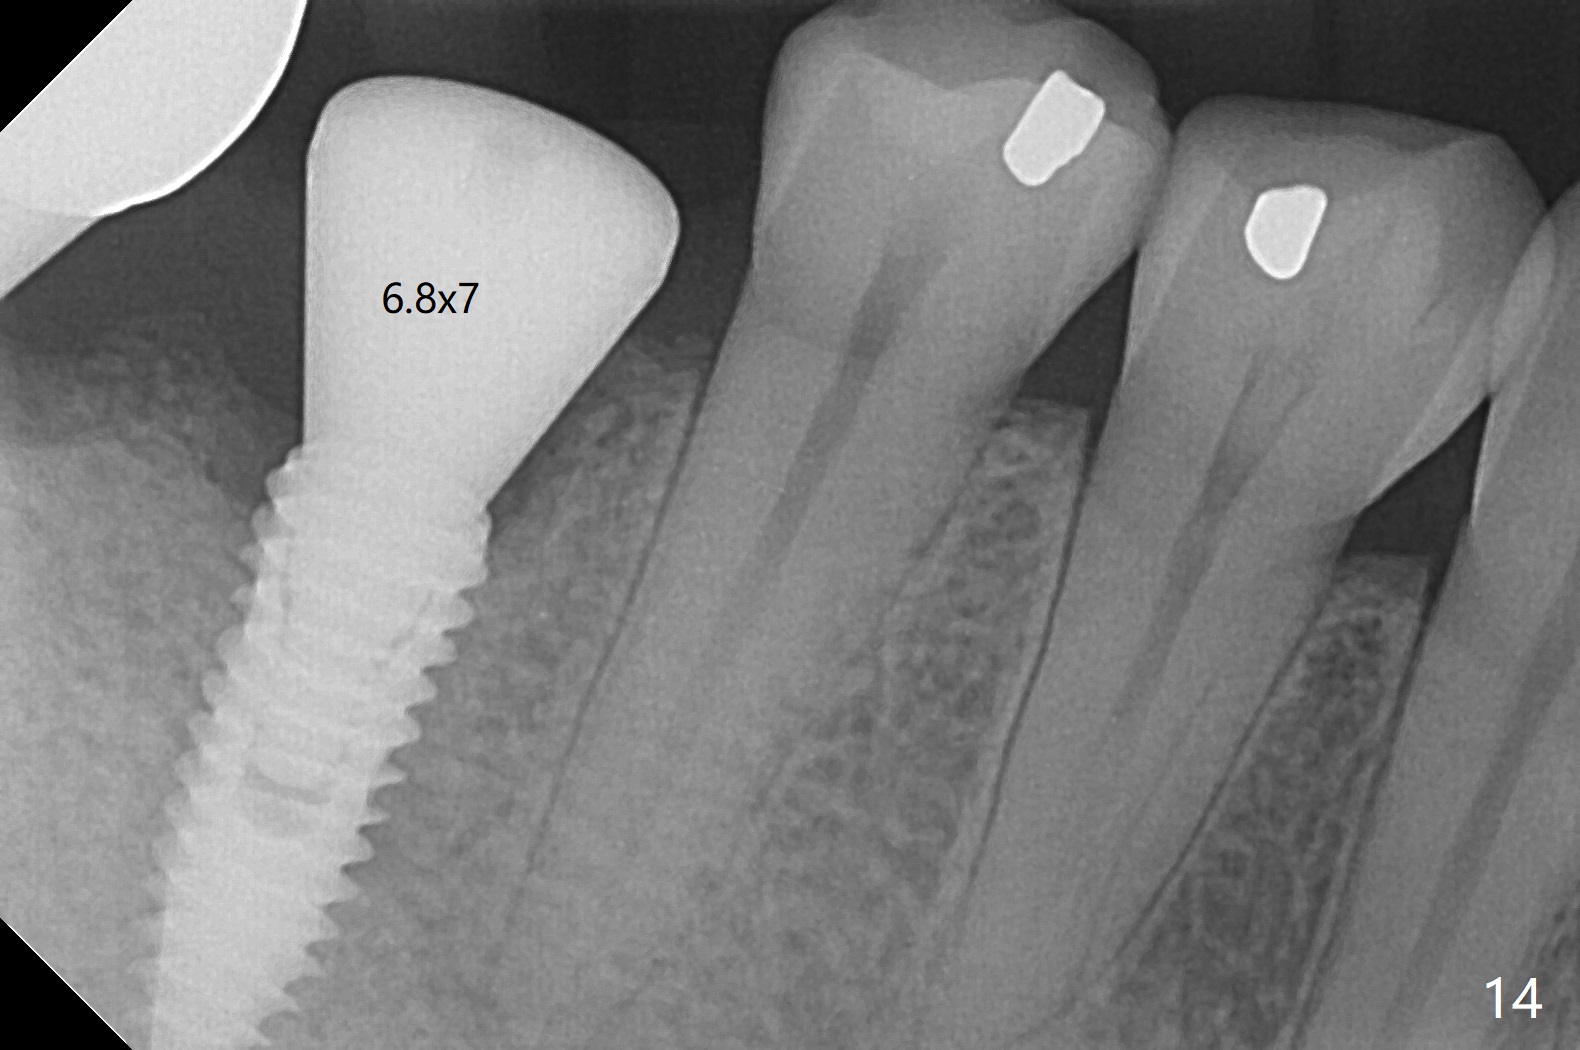

Infection is not so typical.  There is no recent postop X-ray, just 18-19 days postop.   Thanks for the reply.  We will keep watching.  The healing abutments, loose and associated with gingival inflammation, are removed 2.5 months postop (Fig.4).  There is crestal bone resorption, although the implants are stable.  The crestal bone resorption persists especially #30 distal 4 months postop (Fig.5 *).  When the implants are uncovered, there is mild bone loss distobuccal to #30 implant, consistent with early periimplantitis.  Bone graft is placed after debridement and healing abutment placement.  There appears no bone loss nearly 9 months postop (Fig.6).  The soft tissue looks healthy.  Cementation abutments (5.7x4(3) and 5.7x4.5(3) mm at #30,31, respectively) are placed for impression.  The distobuccal gingiva at #30 is hyerplastic 10 months postop (Fig.7 *, immediately before cementation), which is consistent with bone loss (Fig.8,9 * (periimplantitis)).  It is hoped that the infection will dissolve with improved oral hygiene (water pik) over the smooth final restoration.  In fact it is, i.e., the implants at #30 and 31 remain asymptomatic with the healthy gingiva 6 months post cementation (Fig.10,11).  There is mild crestal bone loss at #30 and 31 ten months post cementation (Fig.12).  Crown/implant ratio is the basis for screw loosening.  In fact the crown/abutment at #30 is loose 4 months later.  Incomplete seating of the abutment may be a culprit (Fig.12).  The gingival cuff is not healthy; a 6.8x7 mm healing abutment is placed with gingival blanching with Cetacaine and antibiotic ointment.  Next visit place a new smaller diameter abutment (4.5 or 5.2) with probably longer cuff (4 mm) or the existing abutment with no proximal contact crown, torque 25-30 Ncm and take BW with sensor 2 or PA with sensor 1.  In fact there is resistance to hand tighten a 4.5x4(4) mm healing abutment, which is due to contact with the mesial crest (Fig.13 *).  After use of 5.5 and 6.0 mm profile drills, the 6.8x7 mm healing abutment is reseated.  The latter appears to contact the mesial crest (Fig.14).  Later a 6x5 mm healing abutment is placed.  New crowns with new abutments are delivered 2 years 3 months postop (post Coronavirus lockdown).